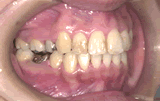

症例3/応用編

矯正歯科治療とかぶせものの歯科治療を併せて行った例です。

【歯科治療前】